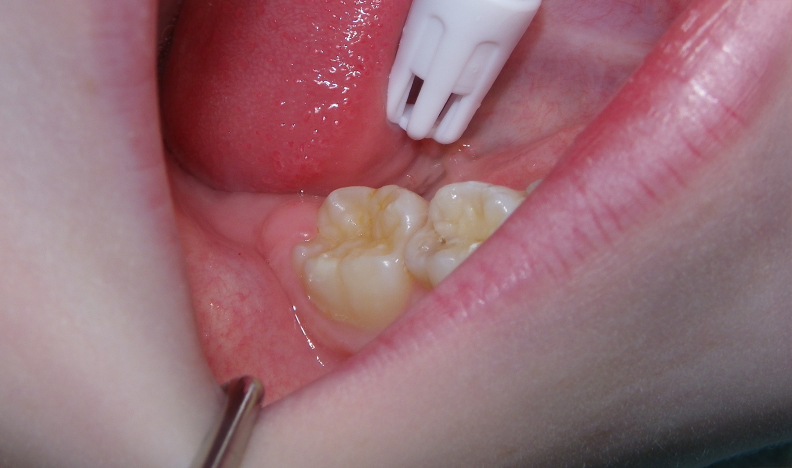

This quick photo series shows the step-by-step process of placing a sealant onto the grooves of an adult molar of a six-year-old. First, air abrasion is used to mechanically remove any loose surface debris or contaminants. Secondly, an acid gel is applied to the surface to be sealed. Finally, a sealant is applied to the surface and allowed to set. For the sharp-eyed, the sealant used was GC Fuji Triage, a glass ionomer sealant that while not as wear-resistant as the more commonly used resin sealants, is more moisture-friendly (ie: contamination resistant) and releases fluoride. The fluoride release allows the underlying enamel to be strengthened over time, making it more decay-resistant for the future.